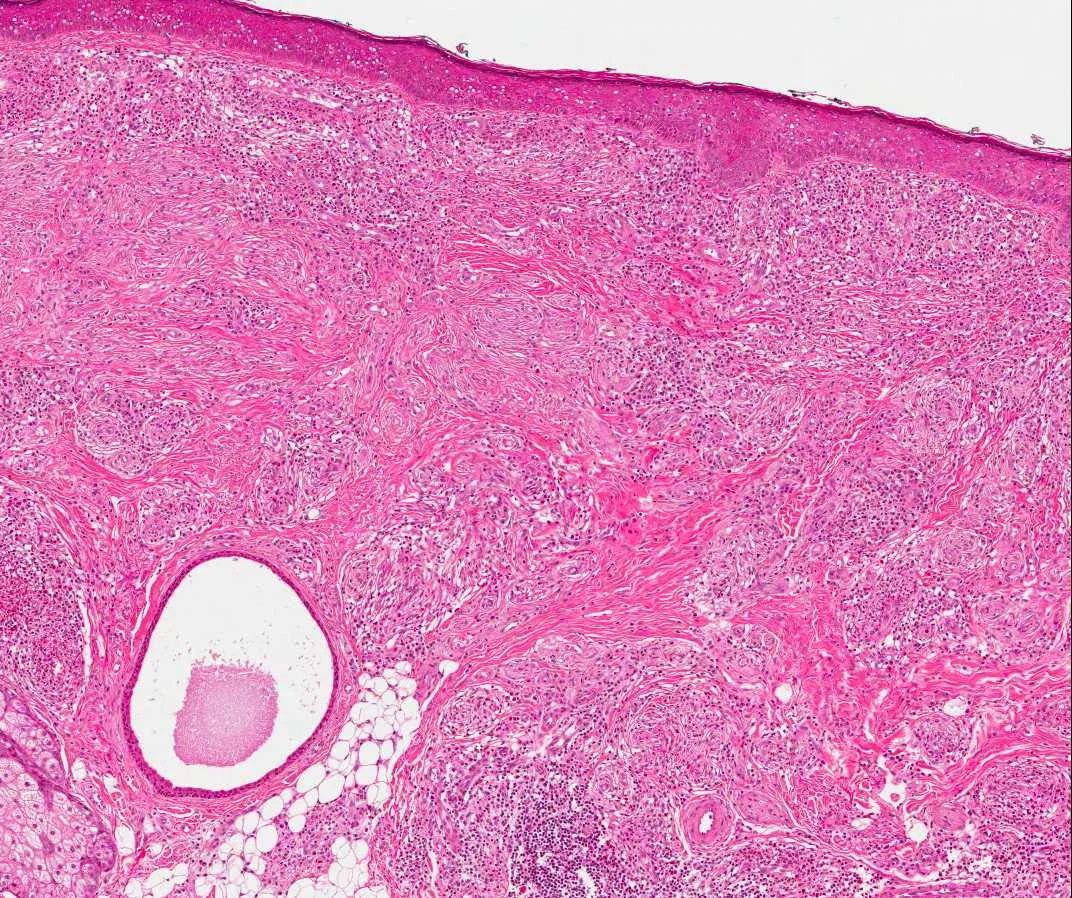

Clinical History: 50 year old male. BCC on the nose.